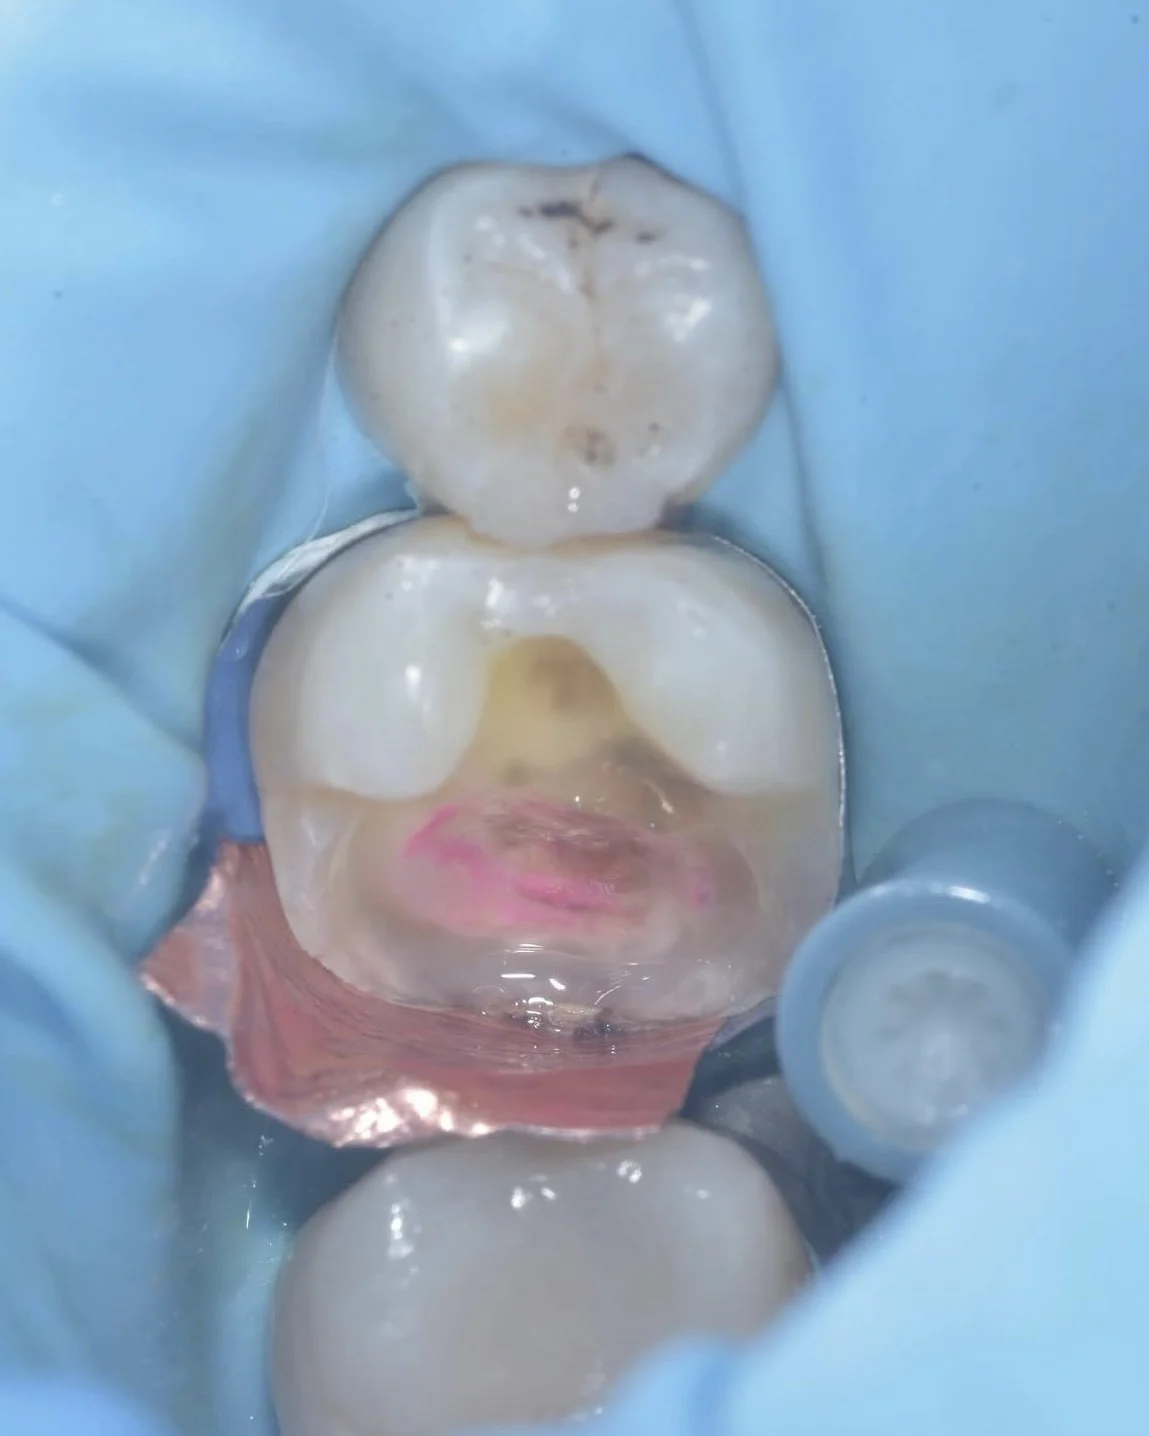

This case by Dr. Davey Alleman, DMD shows the process of removing caries around the pulp to create a caries-free peripheral seal zone.

Use caries detector dye: Caries detector dye is the easiest (and most cost effective) way to objectively see if caries is left behind in your peripheral seal zone. Relying on a tactile approach reduces the consistency of your restorative outcomes.

This case by Dr. Davey Alleman, DMD shows the Six Lessons Approach steps from establishing caries removal endpoints to final cementation.